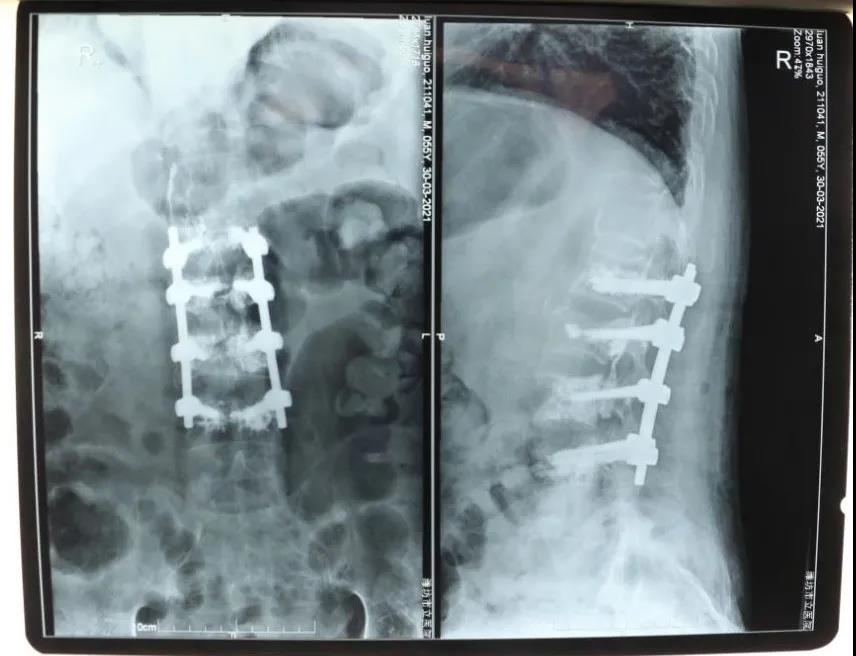

骨一科經(jīng)椎弓根椎體植骨,骨水泥加強(qiáng)釘棒治療

欒先生4天前突然感到腰背部疼痛,活動(dòng)不便,幾天下來也沒有明顯好轉(zhuǎn),于是來到我院就診。經(jīng)拍片檢查發(fā)現(xiàn)欒先生腰椎椎體壓縮性骨折,同時(shí)患者還有重度骨質(zhì)疏松癥。27日,創(chuàng)傷外科主任、骨一科副主任孫守全為患者實(shí)施了椎體壓縮骨折后路切開復(fù)位、椎體植骨、骨水泥注入、釘棒撐開內(nèi)固定手術(shù),成功為患者解除了病痛的困擾。該手術(shù)是我院首例經(jīng)椎弓根椎體植骨,骨水泥加強(qiáng)釘棒治療手術(shù),標(biāo)志著骨科醫(yī)療技術(shù)發(fā)展逐步成熟、不斷攻克新難關(guān),是廣大患者醫(yī)治病痛的可靠力量。